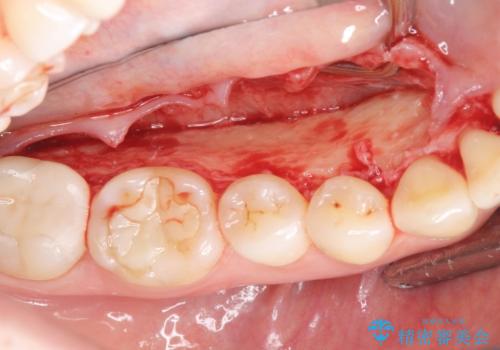

下顎隆起を切除することで舌を収めるスペースを確保し発音のしやすさの向上を図ります。

手術は約1時間弱で終了し、術後もほとんど腫れは出ません。